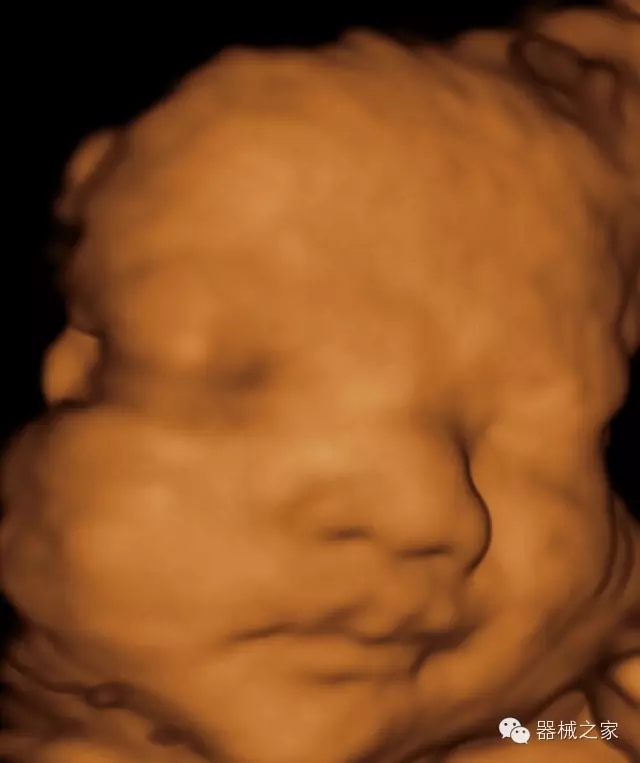

經(jīng)典產(chǎn)品:VINNO 6

臨床圖片賞析

產(chǎn)品特點(diǎn)

·獨(dú)有的RF平臺(tái)提高微小細(xì)節(jié)顯示、圖像對(duì)比度和邊界清晰度;

·特有的XCEN探頭,超寬的帶寬,表現(xiàn)更高分辨率和對(duì)比度;

·單晶純凈波探頭提供更佳的穿透力和彩色敏感度;

·完整的3D/4D臨床應(yīng)用,STIC, MCUT 和Auto NT等滿足產(chǎn)科所有應(yīng)用;

·更高的HQ羊膜腔鏡成像技術(shù)精細(xì)觀察每一個(gè)暗區(qū)細(xì)節(jié);

·智能的觸摸屏界面,能任意角度方位旋轉(zhuǎn)3D圖像,以及注釋快速標(biāo)記,提供直觀與便捷的操作,提高了工作效率;